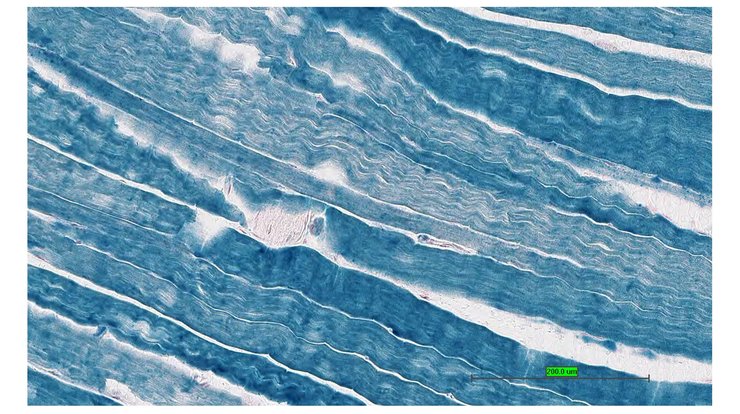

TS28: quadriceps femoris muscle Present UC Davis_1880937

TS28: quadriceps femoris muscle Present UC Davis_1880938

TS28: quadriceps femoris muscle Present UC Davis_1880939

TS28: quadriceps femoris muscle Present UC Davis_1880940

TS28: quadriceps femoris muscle Present UC Davis_1881011

TS28: quadriceps femoris muscle Present UC Davis_1881012